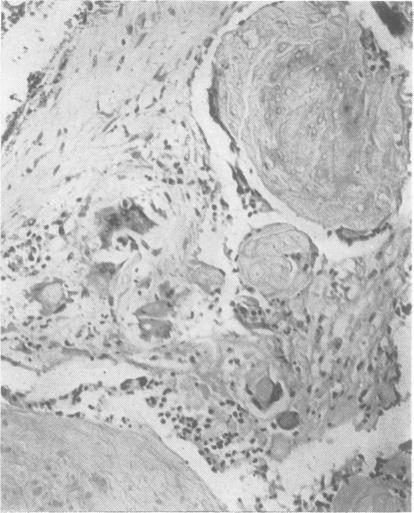

EXPERIENCES WITH RADIOACTIVE GOLD IN THE TREATMENT OF CRANIOPHARYNGIOMA.

J Neurol Neurosurg Psychiatry. 1965 Feb;28(1):30-8. doi: 10.1136/jnnp.28.1.30.